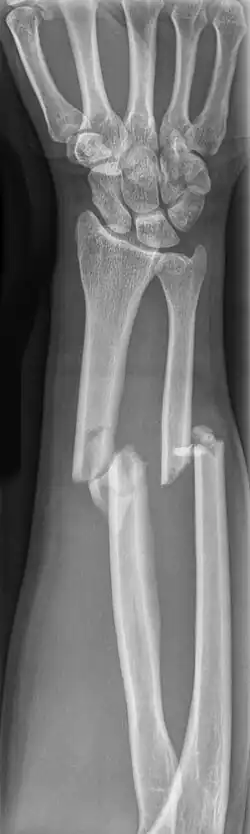

Diese Knochen sind Röhrenknochen. Die Elle ist am oberen, die Speiche am unteren Ende „dick“; denn die Elle bildet mit dem Humerus das eigentliche Ellbogengelenk und die Speiche trägt das Handgelenk (die proximalen Handwurzelknochen). Übertragen wird die Last (z. B. beim Liegestütz) durch die Membrana interossea antebrachii zwischen den beiden Knochen.

„Komplette Unterarmfrakturen“ (beider Knochen) sind bei Kindern häufiger als bei Erwachsenen.